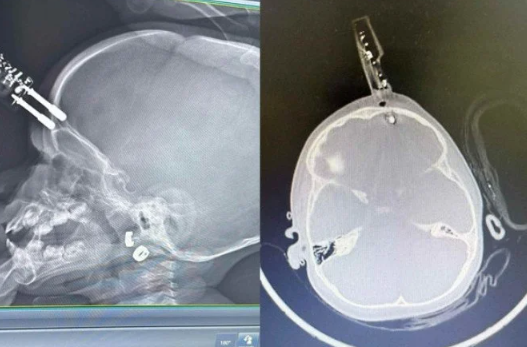

Carregador fica preso no crânio de bebê - (crédito: Cedido ao Correio)

Um acidente doméstico grave envolvendo uma criança de 1 ano e 4 meses mobilizou equipes médicas em Divinópolis, no Centro-Oeste de Minas Gerais. O bebê caiu da cama dentro de casa e acabou tendo um carregador de celular cravado na região frontal do crânio, com perfuração até o cérebro. Apesar da gravidade, a criança passou por cirurgia de emergência e apresentou evolução clínica positiva, recebendo alta hospitalar após alguns dias de internação.

Segundo informações médicas, a criança estava sobre a cama quando caiu no chão do quarto. Próximo ao local havia um carregador comum de celular. Durante a queda, um dos pinos metálicos do carregador atravessou a testa do bebê, atingindo a região frontal do crânio, próxima aos olhos.

Exames de imagem confirmaram que o pino metálico transfixou o osso do crânio, que em crianças dessa idade ainda é extremamente fino, e atingiu o lobo frontal do cérebro.